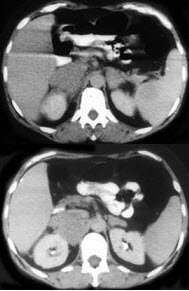

男,65岁,腋下触及肿大包块,全身浅表淋巴结肿大,请结合所提供图像,选择最佳答案( )

A:双侧肾上腺腺瘤

B:双侧肾上腺增生

C:双侧肾上腺淋巴瘤

D:双侧肾上腺转移瘤

E:肾上腺癌